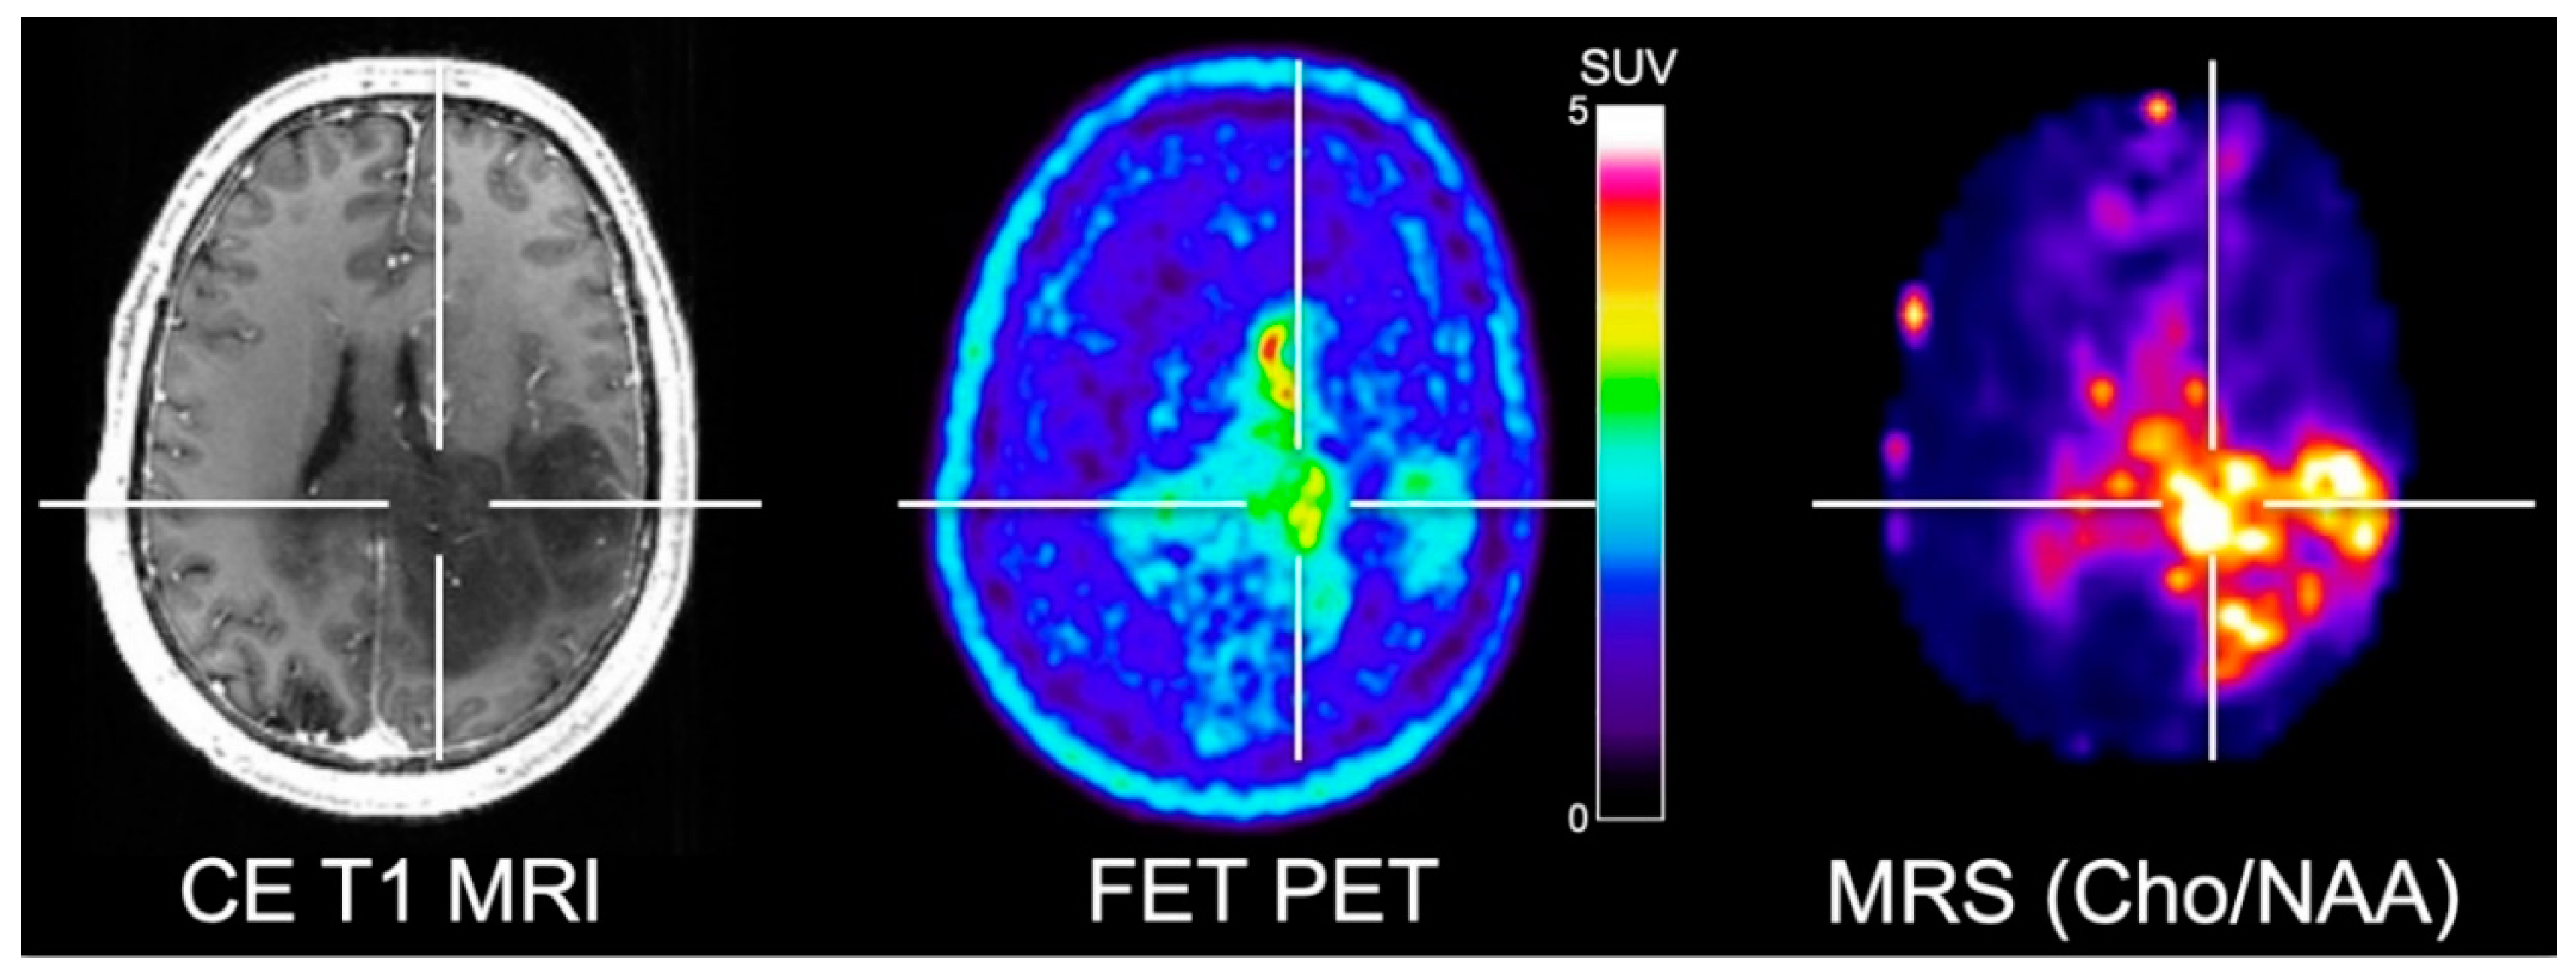

- Floeth, F.W.; Pauleit, D.; Wittsack, H.J.; Langen, K.J.; Reifenberger, G.; Hamacher, K.; Messing-Junger, M.; Zilles, K.; Weber, F.; Stummer, W.; et al. Multimodal metabolic imaging of cerebral gliomas: Positron emission tomography with [18F]fluoroethyl-l-tyrosine and magnetic resonance spectroscopy. J. Neurosurg. 2005, 102, 318–327. [Google Scholar] [CrossRef] [PubMed]

- Stadlbauer, A.; Prante, O.; Nimsky, C.; Salomonowitz, E.; Buchfelder, M.; Kuwert, T.; Linke, R.; Ganslandt, O. Metabolic imaging of cerebral gliomas: Spatial correlation of changes in O-(2-18F-fluoroethyl)-l-tyrosine PET and proton magnetic resonance spectroscopic imaging. J. Nucl. Med. 2008, 49, 721–729. [Google Scholar] [CrossRef] [PubMed]

- Mauler, J.; Maudsley, A.A.; Langen, K.J.; Nikoubashman, O.; Stoffels, G.; Sheriff, S.; Lohmann, P.; Filss, C.; Galldiks, N.; Kops, E.R.; et al. Spatial Relationship of Glioma Volume Derived from (18)F-FET PET and Volumetric MR Spectroscopy Imaging: A Hybrid PET/MRI Study. J. Nucl. Med. 2018, 59, 603–609. [Google Scholar] [CrossRef]